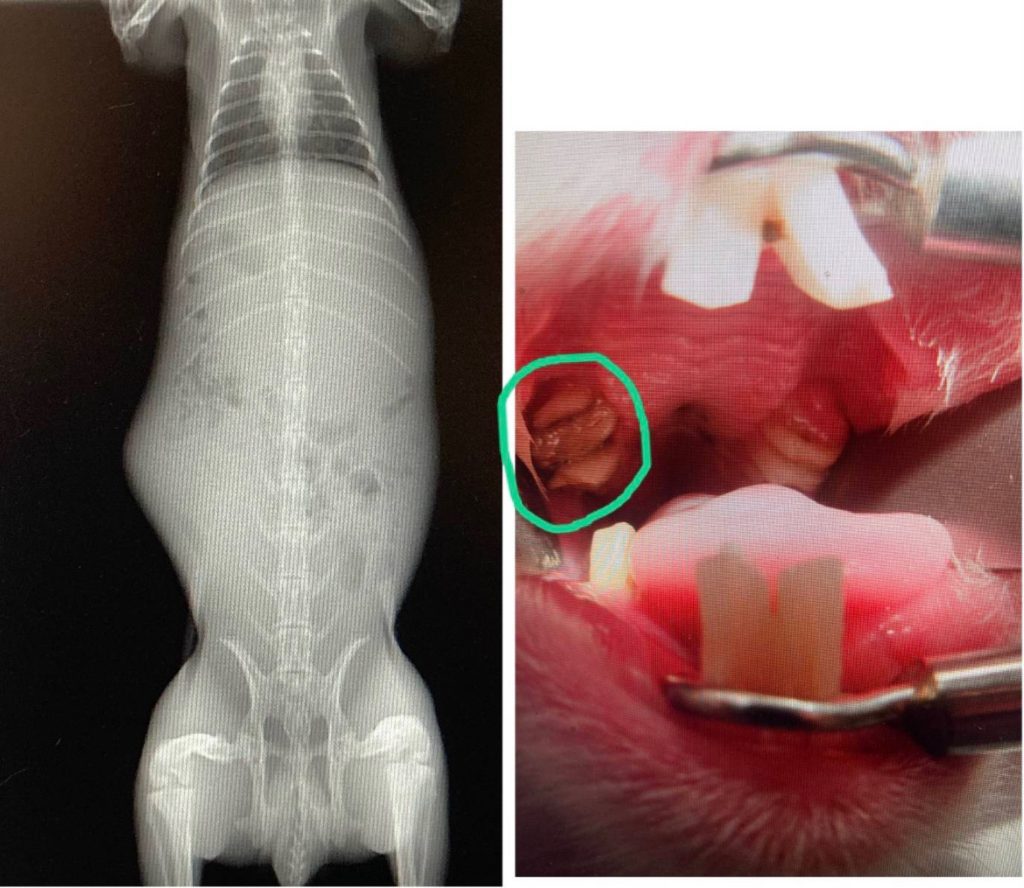

食欲不振と言っても原因は様々であり、消化管鬱滞、急性胃拡張、歯の不正咬合、腎不全、神経症状による二次的な食欲の低下など

多岐にわたります。